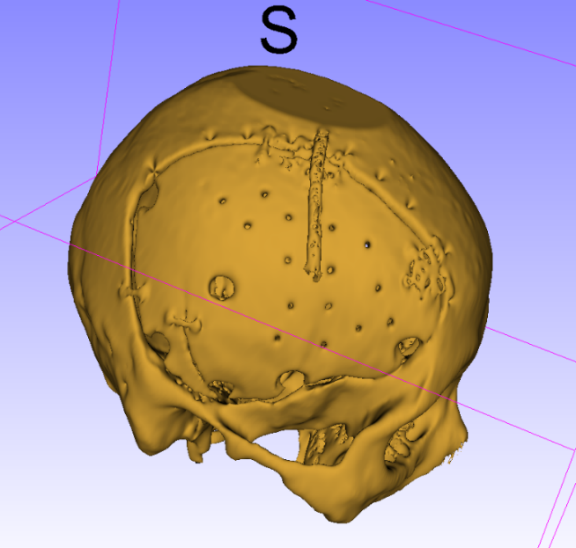

术中情况: